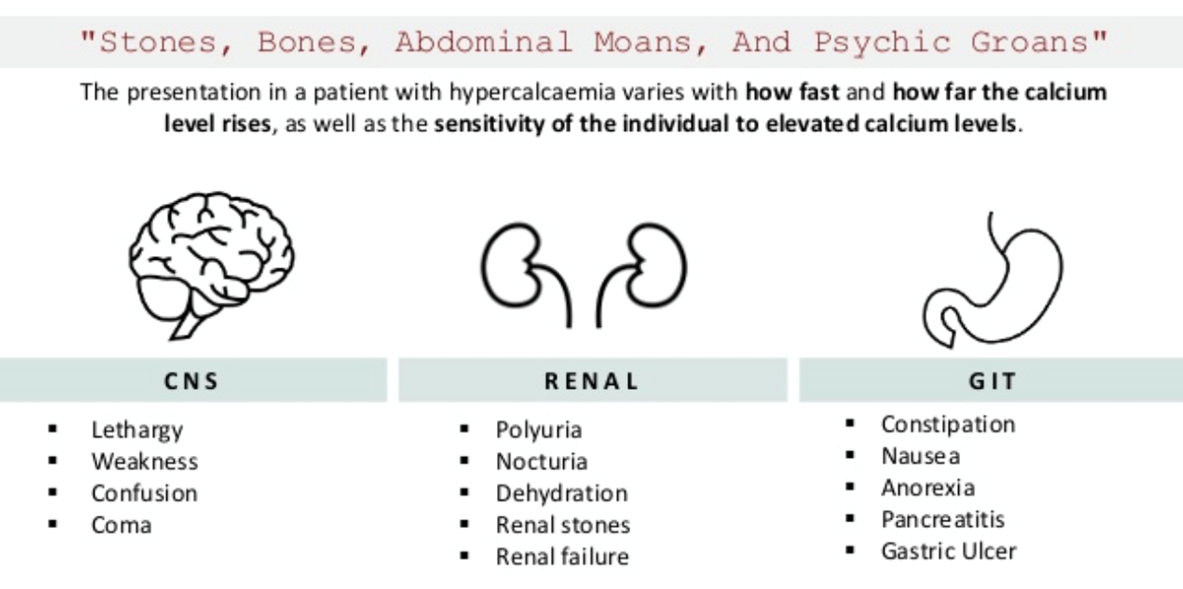

Clinical Manifestations: “Bones, Stones, Moans, Groans”

Stones

- Kidney stones and nephrocalcinosis

Moans

- Abdominal pain

- Renal pain

Groans

- Psychological manifestations: depression, stress

Clinical features

- Renal calculi or renal calcification – occurs in 20% of patients, polyuria (‘renal stones’).

- Bone pain or deformity, osteitis fibrosa cystica, pathological fractures (‘painful bones’).

- Muscle weakness, anorexia, intestinal atony, psychosis (‘psychic moans’).

- Peptic ulceration and pancreatitis (‘abdominal groans’).

Symptoms of hypercalcemia